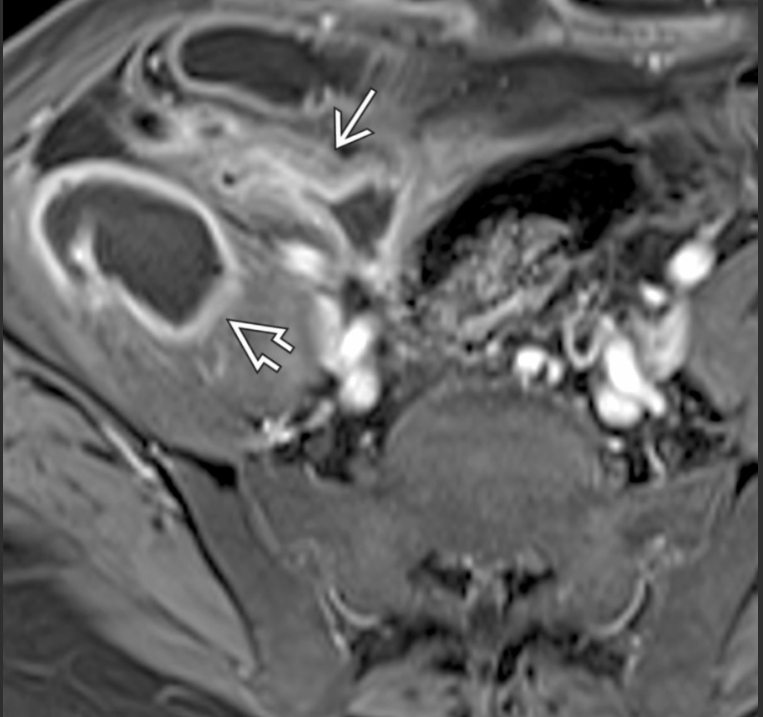

A __________ (doença de Crohn/retocolite ulcerativa) envolve todas as camadas intestinais, podendo resultar em fístulas.

A __________(doença de Crohn/retocolite ulcerativa) tem inflamação confinada à mucosa e submucosa do intestino grosso.

Doença de Crohn; retocolite ulcerativa.

Fístula entre alças de intestino delgado em paciente com Crohn; a alta resolução de partes moles da RM ajuda a delimitar melhor fístulas pequenas.